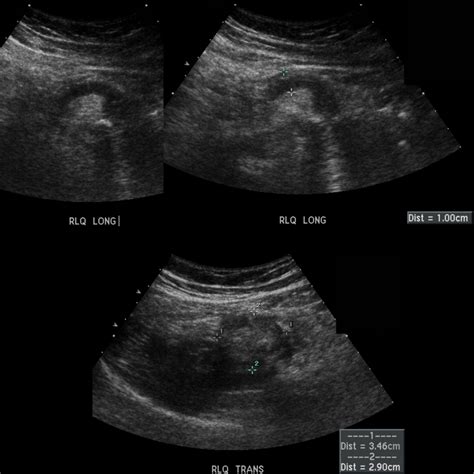

• Appendiceal Diameter: A normal appendix is typically less than 6 mm in diameter. An inflamed appendix will often be larger than 6 mm.

• Appendiceal Wall Thickness: The wall of the inflamed appendix may appear thicker than normal.

• Probe Placement: The ultrasound probe is placed on the right lower quadrant of the abdomen, where the appendix is located.